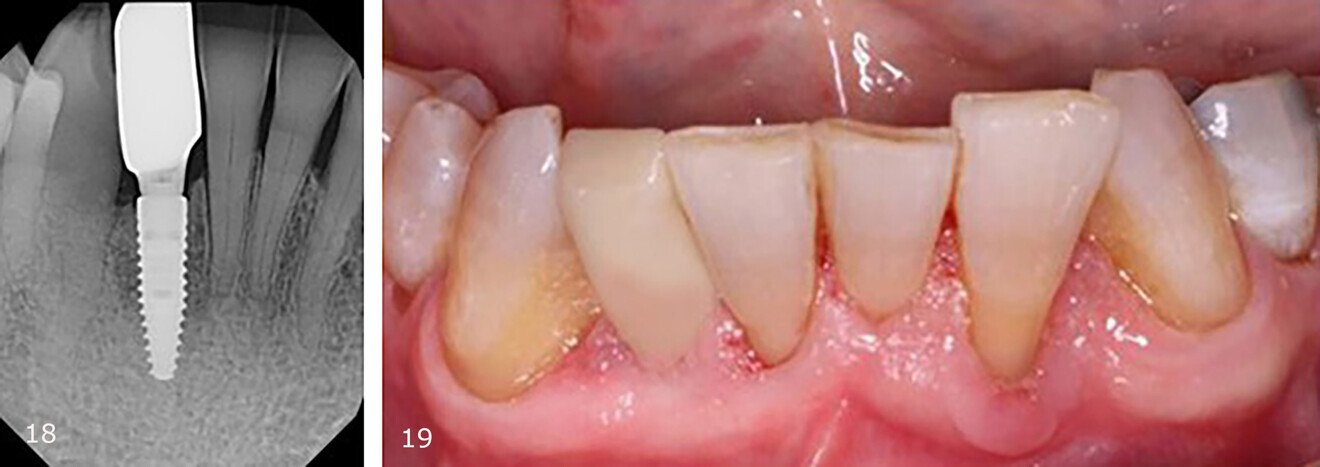

Fig. 18: Periapical radiograph of the restored implant, demonstrating good implant placement with respect to the anatomy in the narrow site. Fig. 19: Implant restoration in situ.

The restorative phase of treatment was initiated after three months of osseointegration. Restoration was completed with a screw-retained crown. A periapical radiograph was taken to confirm seating of the implant restoration on the platform (Fig. 18). Radiographically, it was noted that the bone level on the mesial and distal aspects was at the top of the platform and that there was complete bone fill on the distal aspect of tooth #41. Clinically, the gingiva was healthy and keratinised and presented with no inflammation (Fig. 19).